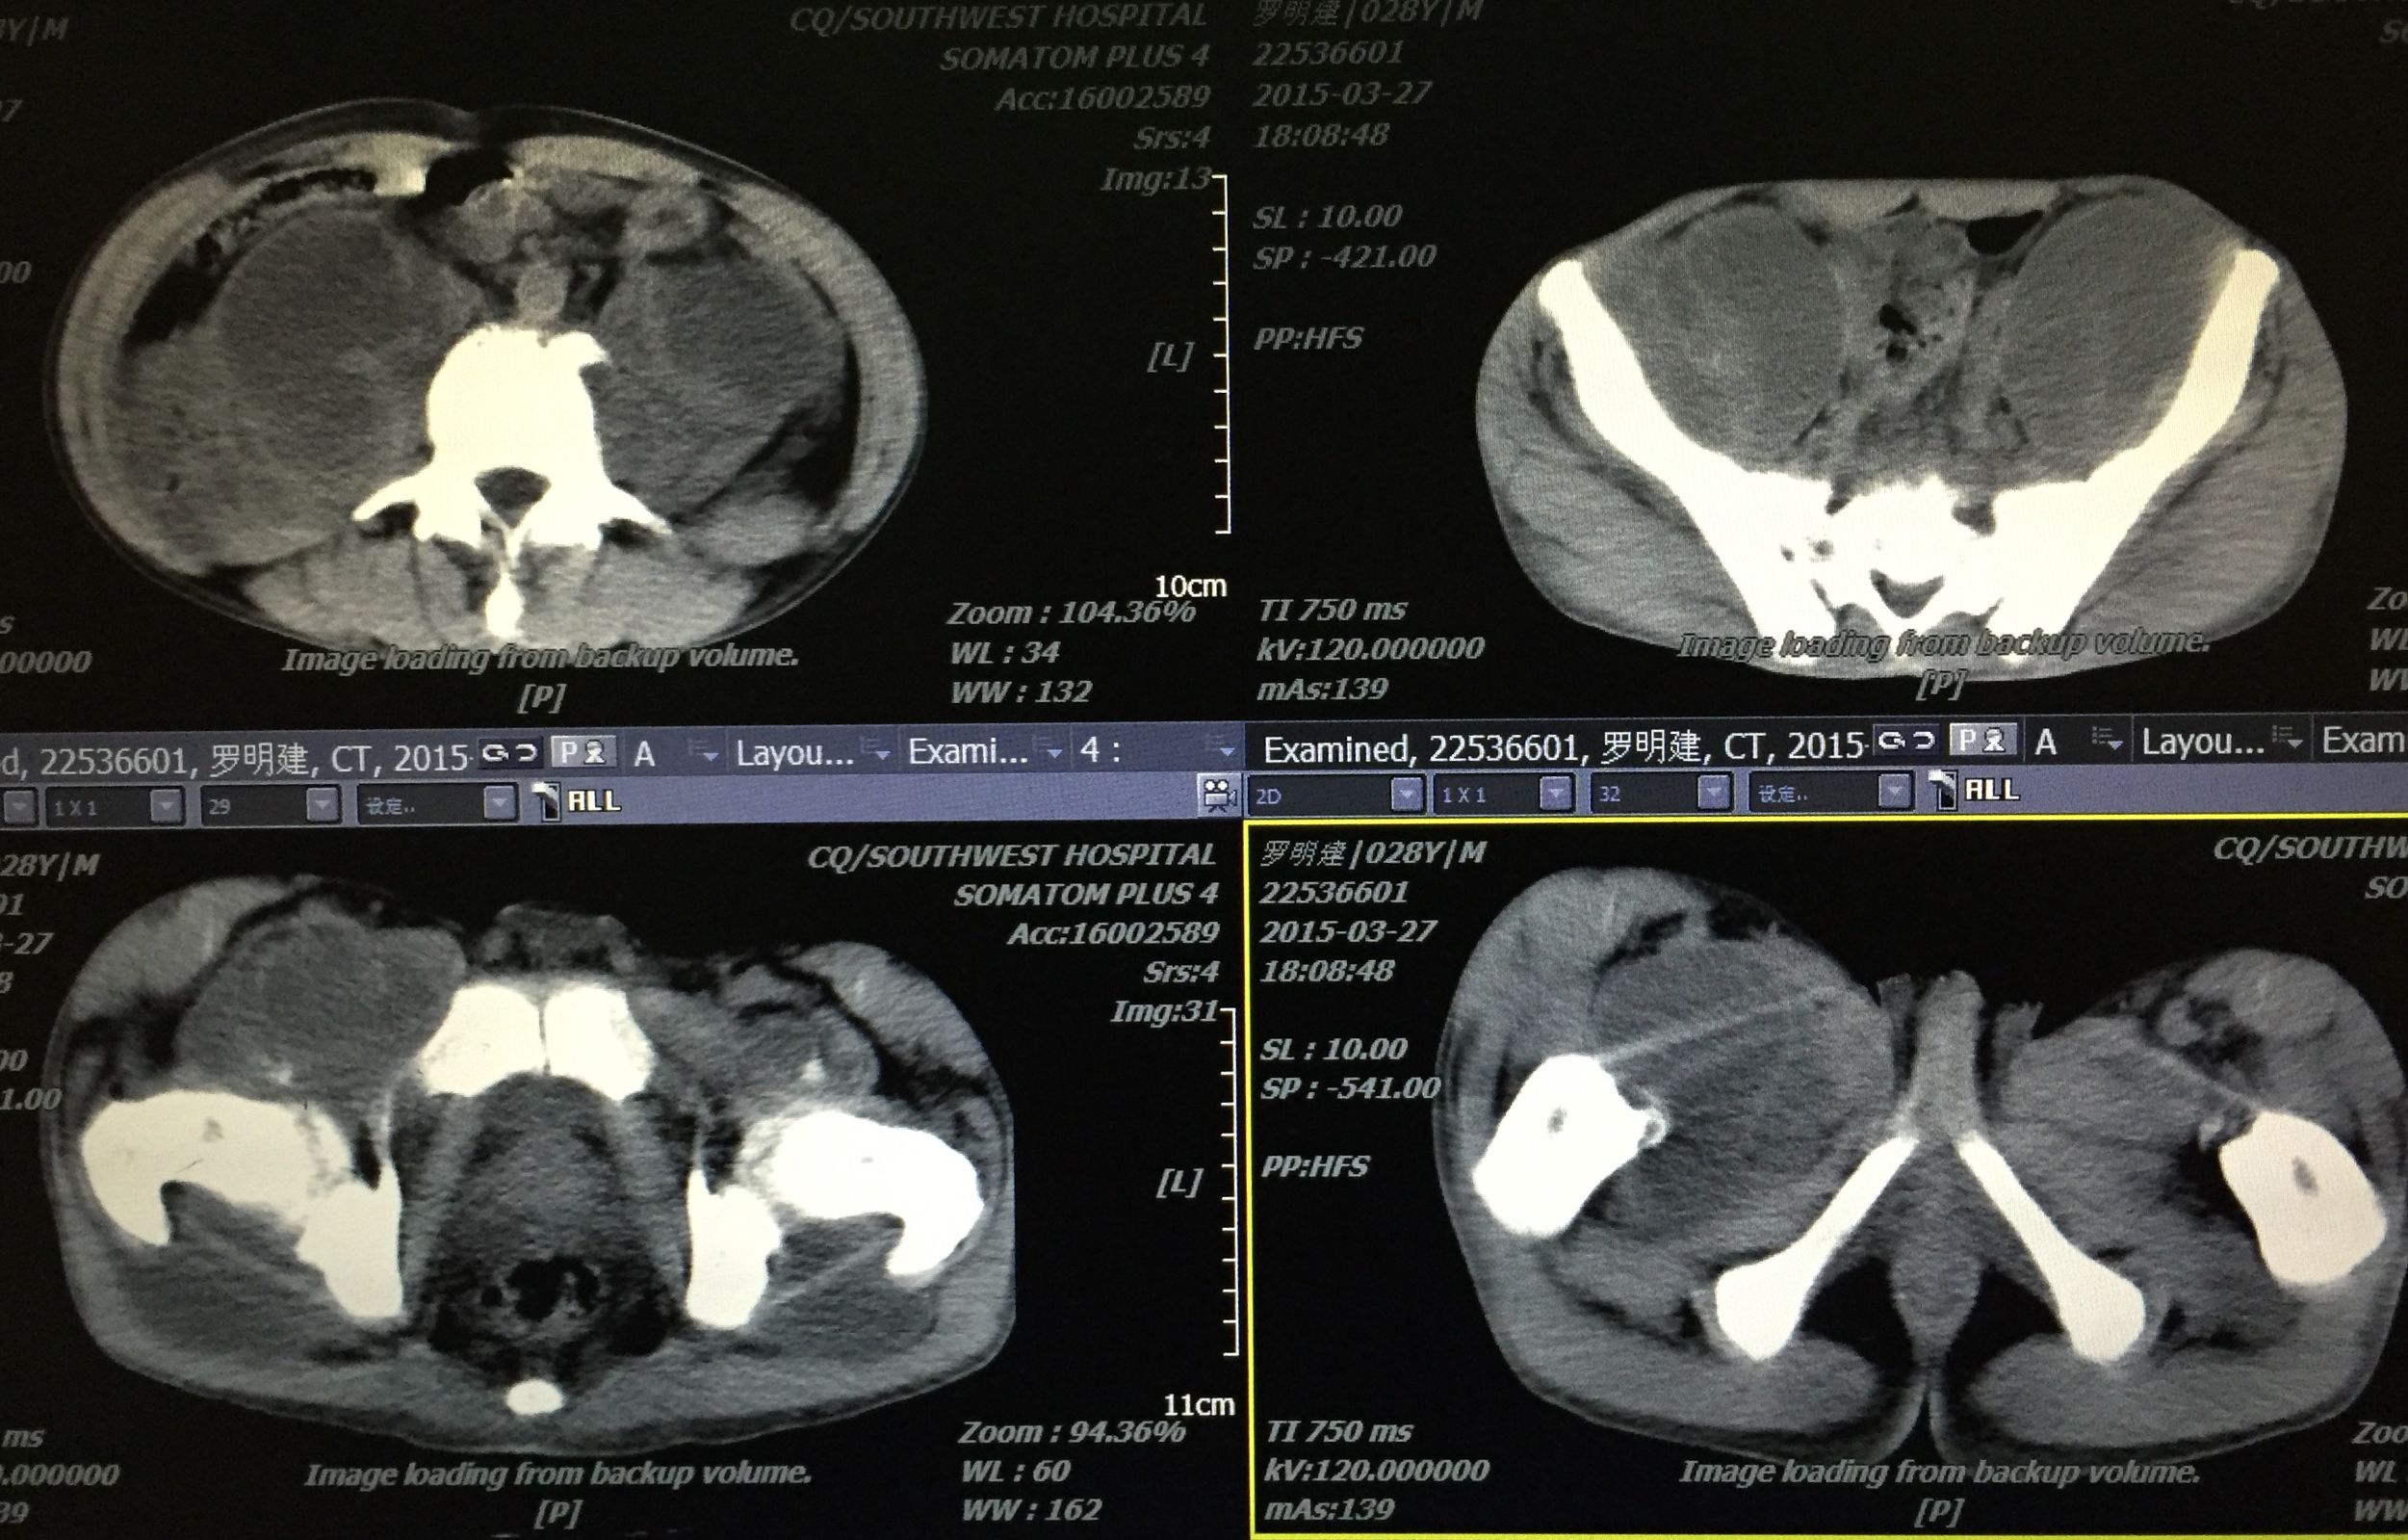

在门诊进行CT引导下穿刺引流术,植入五根引流管(如图白色条状物)

植入一月后,拔出两个引流管,剩余三根引流管仍有脓液溢出。

三月后患者全部拔出引流管。继续抗痨治疗

PS:结核脓肿出现,若能充分引流,可缩短预后时间。CT引导下穿刺引流是各部位脓肿引流较好的处理方案,微创、经济、患者耐受、门诊进行处理。